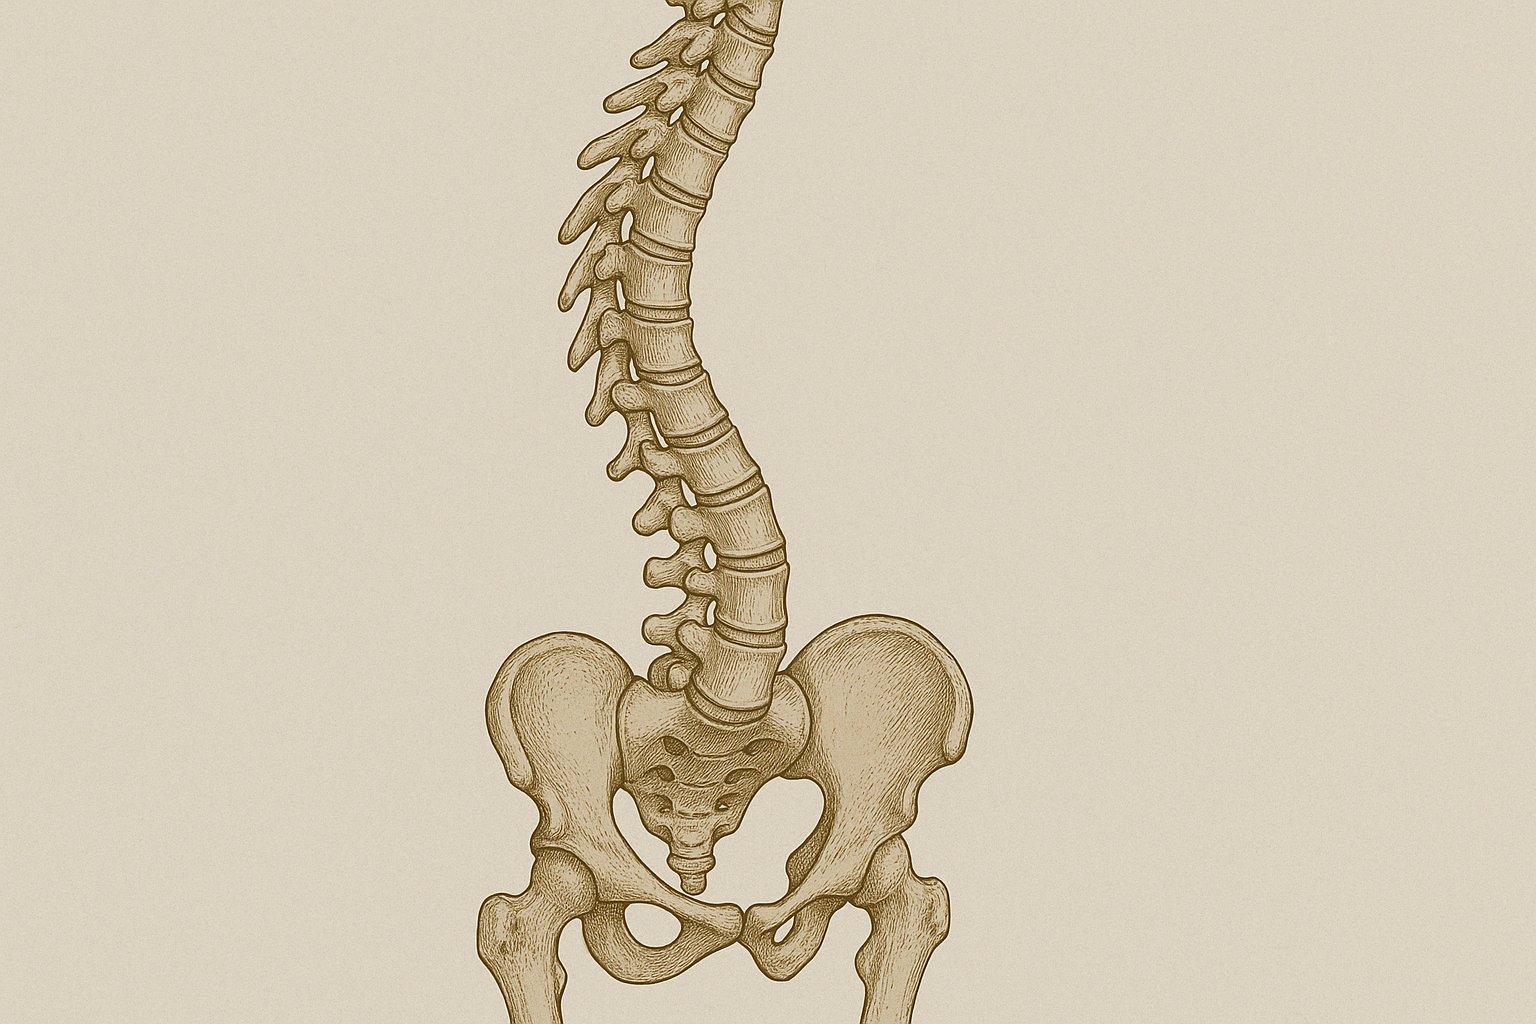

内臓・血流の問題による反射性の不調

体の右側だけに不調が出る背景には、内臓の働きや血流の状態が関係している場合があると言われています。特に右側には肝臓や胆のうなどの臓器が位置しており、それらの不調が体表面の筋肉や神経に影響を与えることがあるそうです(引用元:https://bianca-hari.com/column/right-side-symptoms/)。この現象は「内臓体性反射」と呼ばれ、内臓の異常が脳や脊髄を介して筋肉のこわばりや痛みとして現れると説明されています。

例えば、肝臓の疲れや血流の滞りは、右肩から背中にかけての違和感やだるさとして感じられることがあるとの見解があります。これは単なる筋肉疲労とは異なり、内臓からの信号が神経を通じて筋肉の緊張を引き起こすケースです(引用元:https://www.madoka-seitai.in/posture-improvement/body-distortion/1009/)。また、消化器系の不調や長期的な生活習慣の乱れも、右半身の特定部位に影響を与える可能性が示されています。

実際の症例として、慢性的な右腰の痛みを訴えて来院した方が、詳しい触診や検査で肝機能の低下や胆のうの不調が見つかったという報告があります(引用元:https://bianca-hari.com/column/right-side-symptoms/)。このように、外見的な姿勢や筋肉の状態だけでは原因が特定しづらく、内臓の健康状態が深く関わっていることも少なくありません。

日常的なケアとしては、バランスの良い食生活、十分な水分補給、適度な運動で血流を促すことが推奨されています。また、右側だけに繰り返し不調が出る場合や、疲労感が強く続く場合は、専門家による触診や内臓の健康チェックを受けることが望ましいとされています。早めに原因を探ることで、長期的な改善につながる可能性があると言われています。